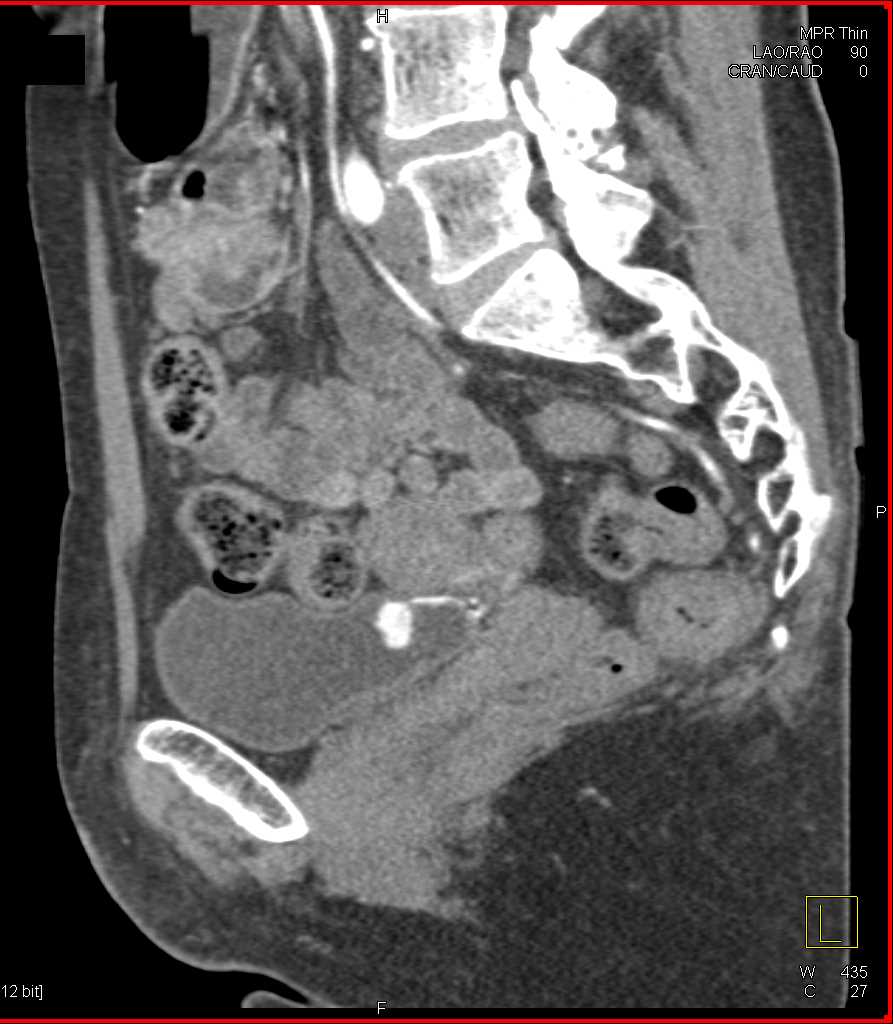

Bladder Cancer with Active Bleed